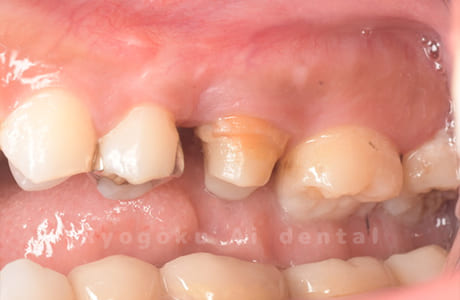

Case21

-

- 原因

- 重度カリエス

- 治療内容

- クラウンレングスニング

- 治療費用

- 44,000円

他院で抜歯と宣告され、当医院を受診された患者様です。クラウンレングスニングを行い、保存を行いました。経過良好です。

<リスク・副作用>

手術後は痛み、腫れ、痺れ、青あざなどの副作用が生じます。痛みは痛み止めを処方しますが、腫れ、青あざは1週間程度生じる場合があります。また、部位によっては神経の走行が複雑で、痺れが残り、長期的にお薬を処方する場合があります。